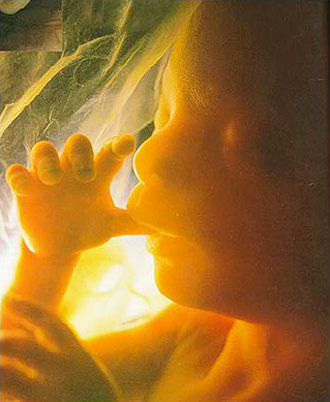

- 임신 증상진단

- 뚜렷한 임신증상이 없을 수 있습니다.

증상:입덧, 피로, 빈뇨, 두통 등 - 임신확인 검사

배란일로 보터 일주일 이후가 되면 임신테스트기로 임신사실이 확인됩니다.